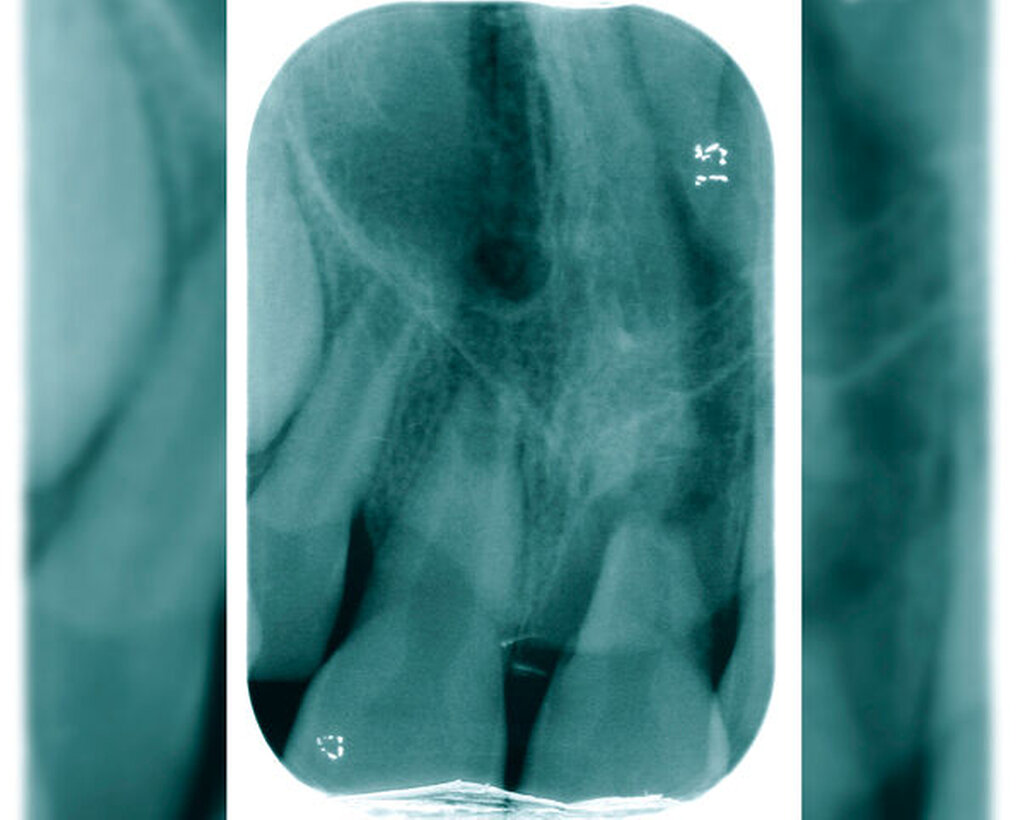

„Ubi pus, ibi evacua!“ – der lateinische Aphorismus wird häufig in vielen Bereichen der Medizin zitiert. Dieser Grundsatz trifft auch auf die Behandlung von akuten apikalen Abszessen zu. Der erste Weg der Behandlung sollte hier, wann immer möglich, über den Wurzelkanal gehen, um eine Drainage für den Pusabfluss zu schaffen (Abbildungen 1 und 2). Das nekrotische Pulpagewebe oder die bereits vorhandene Wurzelkanalfüllung gilt es von orthograd zu entfernen. Die Wurzelkanalpräparation kann die Drainage des Abszesses weiter unterstützen. Mittels der chemischen Desinfektion im Zuge eines suffizienten Spülprotokolls erfolgt eine weitere Elimination von Mikroorganismen und nekrotischem Pulpagewebe aus dem Wurzelkanallumen. Zur weiteren Desinfektion und zur Anhebung des pH-Wertes wird eine wässrige Kalziumhydroxideinlage in den Wurzelkanal eingebracht. Ein „Offenlassen“ des Zahnes nach der Schmerzbehandlung gilt es zu vermeiden, da sich Mikroorganismen aus der Mundhöhle im Wurzelkanal ansiedeln und nachfolgend zu einem Biofilm kolonialisieren können [Siren et al., 1997]. Lässt sich der Pusabfluss aus dem Wurzelkanal nicht stoppen, kann ein Zahn in Ausnahmefällen für maximal 24 Stunden offengelassen, am folgenden Tag in der Praxis endodontisch versorgt und mit einem provisorischen Verschluss versehen werden [Schäfer et al., 2021].